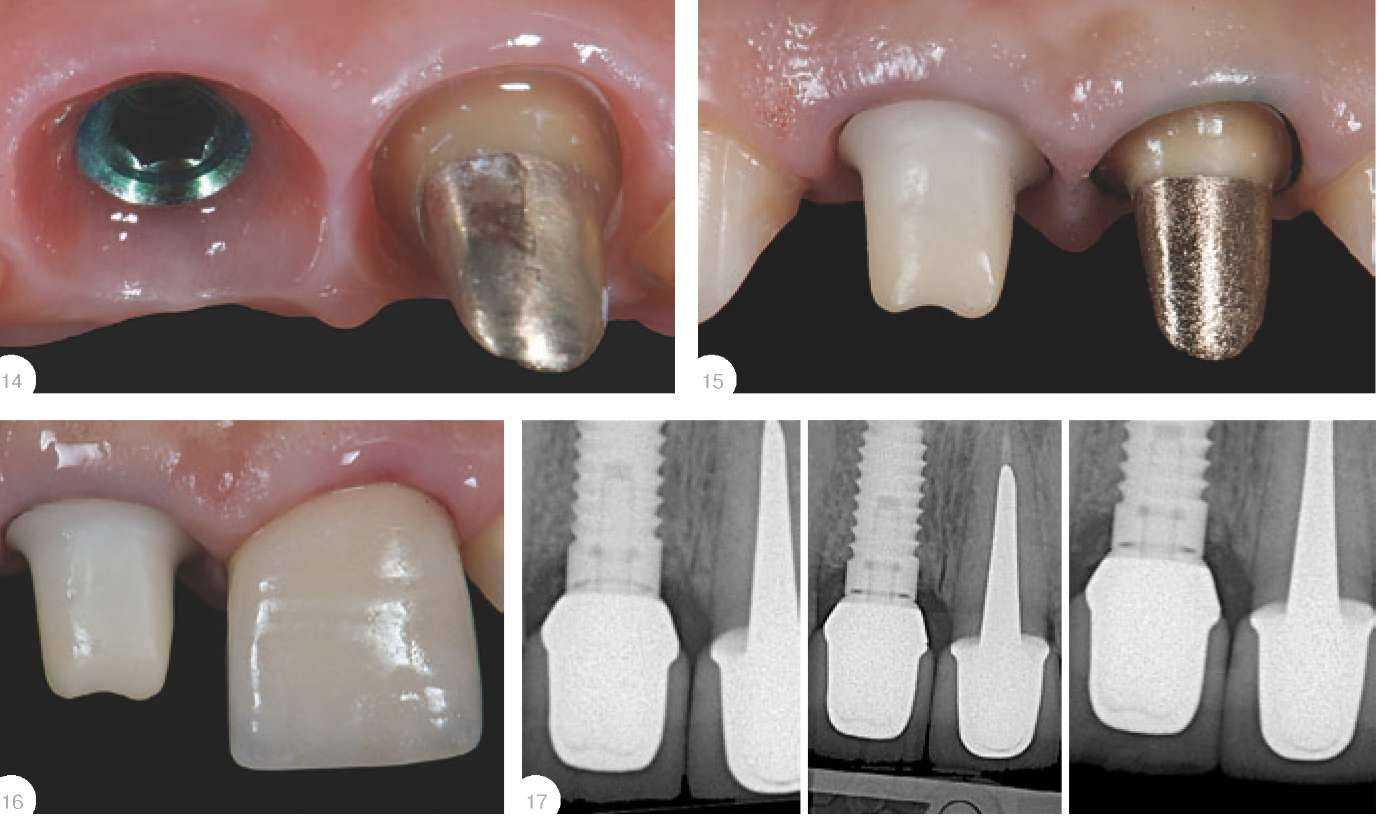

Винтовая фиксация Коронки с винтовой фиксацией могут быть изготовлены как прямым методом непосредственно врачом в клинике во время приема пациента, так и лабораторным путем. Умение применять прямой методявляется необходимым инструментом в арсенале ортопеда, который можно применить либо всилу удаленности лаборатории отклиники, либо в случае непредвиденного удаления и установки имплантата, и невозможности отпустить пациента без временной реставрации. К преимуществам прямого методанад лабораторным можно отнести возможность контроля необходимой поддержки мягких тканей впришеечной области, низкую себе стоимость, сроки.К недостаткам - не очень высокую либо вовсе низкую эстетику.Надо отметить, что применять метод винтовой фиксации стоит крайне осторожно. Следует ограничить количество откручиваний и прикручиваний таких коронок, особенно при тонком биотипе десны,так как (особенно на плохо отполированных конструкциях) из-за возникающего ложного прикрепленияи постоянной травматизации возможны большие рецессии. Лабораторный метод подразумевает под собой снятие оттиска ипосле получения из лабораториигипсовой модели ремоделирование десневого края согласно необходимому эстетическому контуру (лабораторную методику см.ниже). После того, как акриловыекоронки готовы, врач выполняетанестезию в области имплантатови прикручивает их до наступленияишемии десны (обязателен RVGконтроль). Важно помнить, что данная конструкция должна оказывать давле-ние только на мягкие ткани. В случае такого давления на подлежа-щую кость всегда развиваетсямощнейший болевой синдром спродолжительным воспалением и,как следствие, серьезной рецессией (рис. 12-13). Срок ремоделировки тканей в полости рта занимает от 4 до 6 недель и при достаточном количестве прикрепленной десны всегдадемонстрирует стопроцентный результат, который заключается видеальной имитации естественного десневого края. Однако, еслипланируется также протезирование соседних с имплантатами зубов, врач-стоматолог обязан помнить, что, не погружая уступ поддесневую область с апроксимальных сторон на границе с имплантатами, он рискует потерять десневой сосочек вследствие отсутствия его поддержки.В качестве иллюстрации этих теоретических построений позволюсебе привести небольшой пример. *) Отдавая дань моде, многие врачи изготавливают сегодня коронки издиоксида циркония на витальные зубы во фронтальном отделе, забывая отолщине колпачка будущей реставрации - 0,5 мм! Естественно, что техник для достижения эстетических запросов пациентананесет еще как минимум 1 мм керамической массы, и такая толщинанеизбежно приведет к чрезмерному препарированию! В то же время, применение на витальных зубах прессованных либо полученных на огнеупорных моделях конструкций позволяет врачу поройсохранять до 2/3 эмали (!), что многократно улучшает прогноз выживае-мости выполненной работы. Клинический случай Пациентка 29 лет, 11- перелом внижней трети. После детального разбора ситуации в присутствии зубного техника(Дмитрий Никоненко) принято решение об удалении 11 с одномо-ментной установкой имплантата,временной коронкой с винтовойфиксацией и протезированием 4резцов через 6 месяцев. По истечении этого срока мы приступили к эндодонтическому лечению 21 и изготовлению культевойвкладки. Принято решение изготовить индивидуальный абатмент идве коронки на каркасах из диоксида циркония на зубы 11 и 21, а навитальные 12 и 22 - бескаркасныекоронки толщиной не более 0,5 мм!* (рис. 14-17). Несмотря на превосходную эпителизацию, перед фиксацией коронок необходимо уложить междуабатментом, зубами и десной

ретракционную нить без пропитки диаметром не более 000 или 00 для захвата избытка цемента.Применяя позиционер в RVG, можно увидеть факты «недопосадки»каркаса коронки на абатменте илизубах! Обратите внимание на искаженный снимок 17а, где неопытному врачу может показаться, чтоположение коронки на абатменте идеально, однако при правильном расположении позиционера виднащель в медиально-апроксимальной зоне коронки на 11 зубе. Рис. 18 - зафиксированные на самопротравливающий и самоадгезивный цемент коронки через 7дней. Ситуация через три месяцаприведена на рис. 19. По прошествии года ситуация выглядит таким образом - рис. 20. Ни у стоматолога, ни у техника, ни у пациента нетнареканий к выполненной работе.А ведь это фронтальная зона...